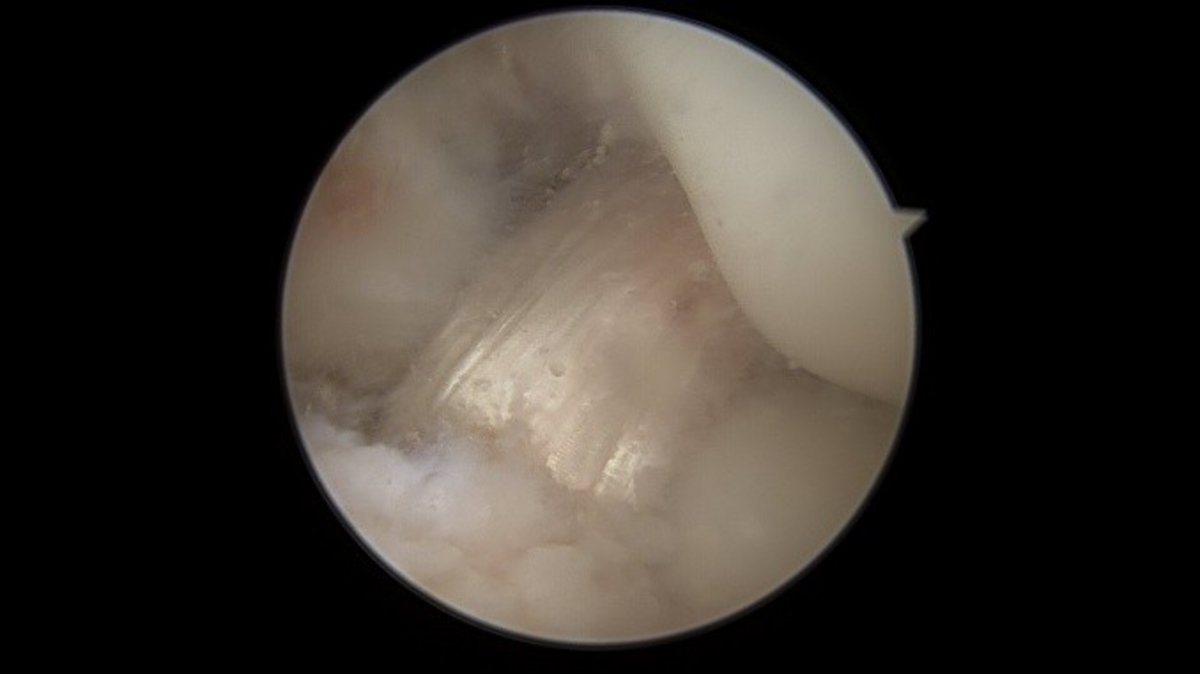

Knorpelschäden

Bei Knorpelschäden unterscheiden wir zwischen degenerativen Veränderungen („Arthrose“) und traumatischen Knorpelschäden. Je nach Größe, Lokalisation und Ursache für die Knorpelschäden wird eine individuelle Therapie abgestimmt. Konservative Therapiemöglichkeiten (Physiotherapie, Infiltrationen, Orthesen, …) sind ebenso eine Möglichkeit, wie die operative Behandlung.

Es ist wichtig, die Ursache für einen Knorpelschaden herauszufinden und ggf. mitzubehandeln. Neben einem Unfall ist auch eine chronische Instabilität oder eine Achsfehlstellung unter Umständen für einen Knorpelschaden verantwortlich – vor einer Knorpelreparatur ist die Behandlung der Ursache essenziell.

Als Behandlungsmöglichkeiten für Knorpelschäden gibt es die sog. Abrasionschondroplastik / Mikrofrakturierung, bei der der defekte Knorpel bis auf den Knochen abgetragen und dieser dann mit kleinen Löchern perforiert und ggf. mit einer speziellen Membran bedeckt wird. Durch die Perforationen tritt Knochenmark in den Defekt ein und es bildet sich ein sog. Regeneratknorpel. Auch die Möglichkeit einer Knorpelzelltransplantation (sog. „ACT“) wird bei uns angeboten. Hier werden in einer ersten Operation Knorpelzellen entnommen und in einer zweiten Operation in den Defekt eingebracht (entweder als sog. ACT Inject in einer Suspension oder als ACT 3d auf einer Membran). Auch die körpereigene Transplantation eines Knochen-Knorpel-Zylinders (OATS / Mosaikplastik) ist eine Therapiemöglichkeit, die wir anbieten können.